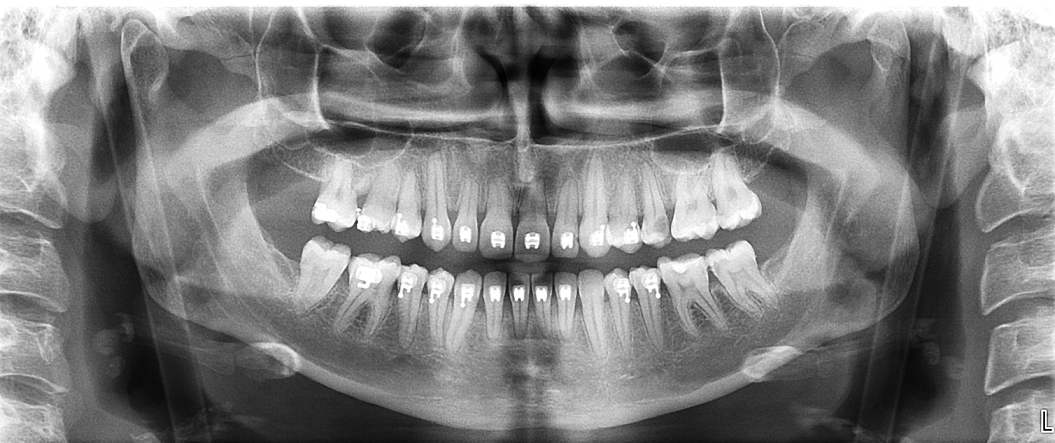

La ortopantomografía es una de las pruebas radiológicas más solicitadas en odontología. Sin embargo, su calidad depende en gran medida

El CBCT (Tomografía Computarizada de Haz Cónico) es una de las herramientas diagnósticas más importantes en la odontología actual. Su